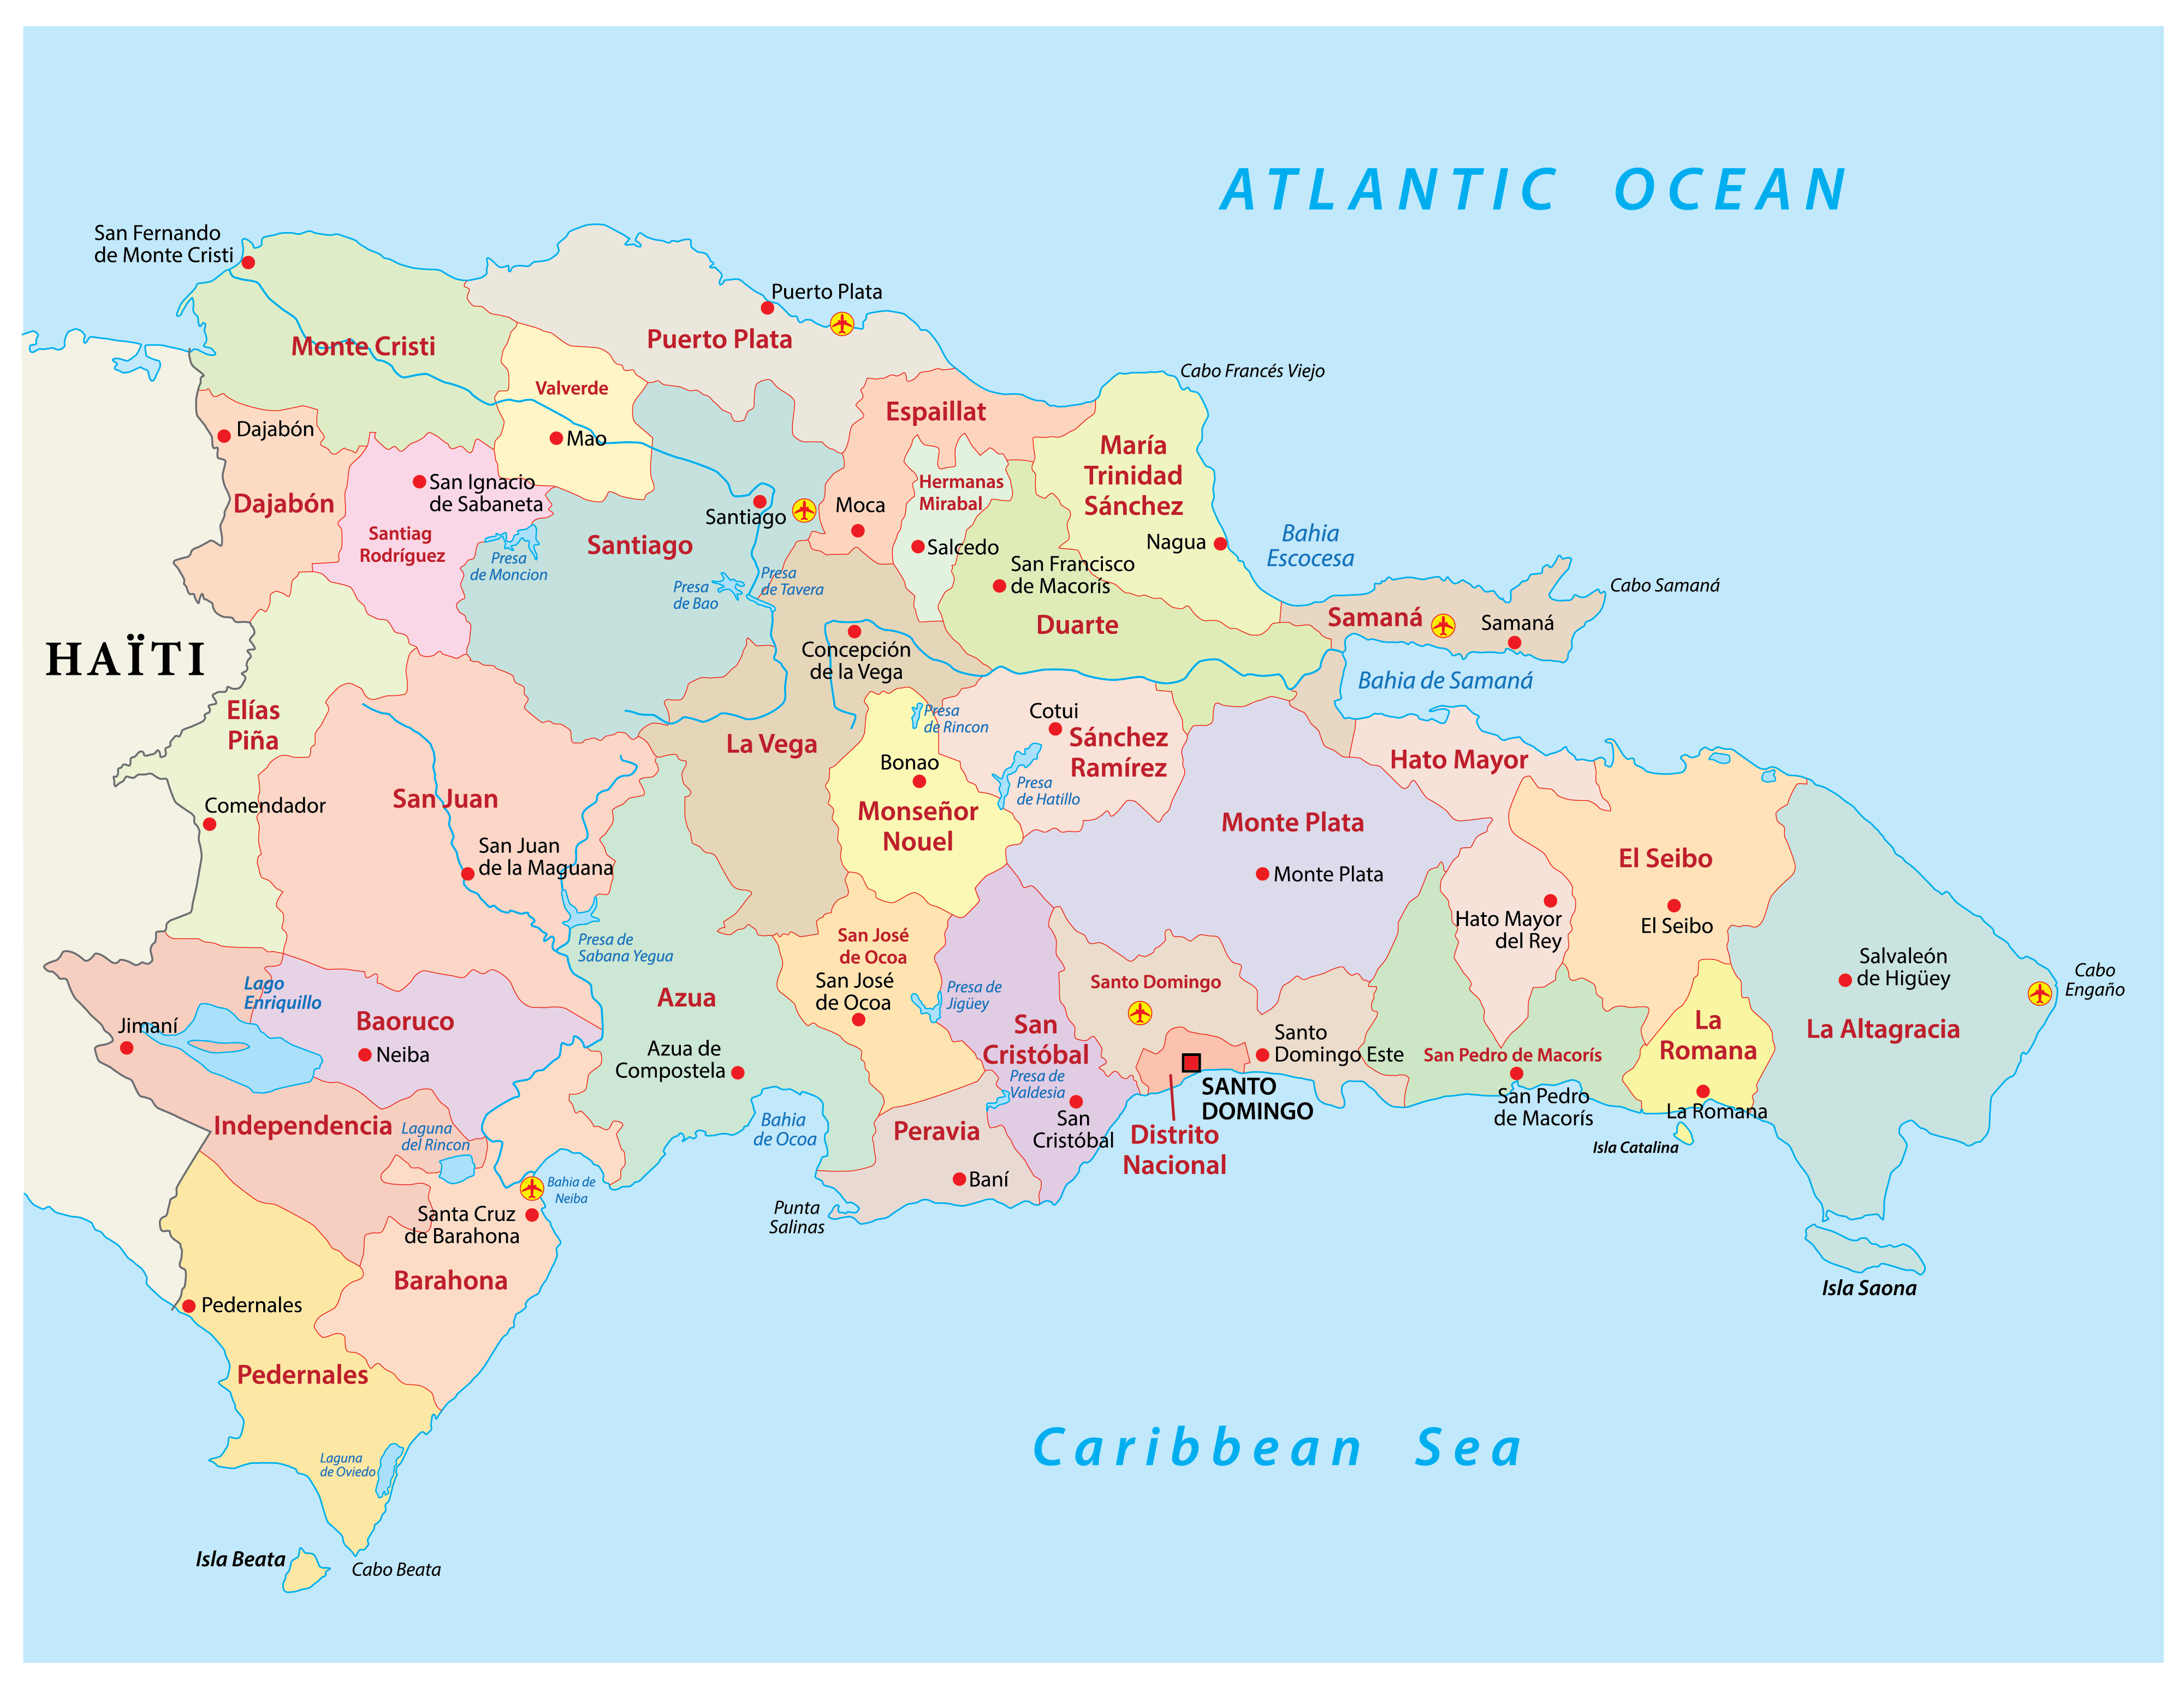

Southern Dominican Republic has seen an increase in Malaria. 984 cases have been reported to date in 2024. Only 265 people were affected last year in the same reporting cycle.

Three provinces recorded the highest incidence of malaria: Azua (485), San Juan (453), and Bahoruco (six).

Malaria when not treated in time can have serious consequences, according to organizations such as the Pan American Health Organization (PAHO), a contagion can cause serious kidney and brain complications in a person, and even death.

Symptoms of the disease can include fever, vomiting and headache. But the classic form of manifestation in the body is with high temperatures, accompanied by sweating and chills, which appear 10 to 15 days after the mosquito bite.

Dengue is another vector-borne disease that is present in the Dominican Republic, where a tropical environment predominates, making it conducive to more than one person having to be assisted in a health center each year for becoming infected.

Mosquitos are man’s greatest acme predator. Mosquito-borne diseases kill more than one million people and infect up to 700 million each year – almost one in ten people. As the planet warms and climate change lengthens the mosquito season, the world’s deadliest creature will expand its geographical range to new regions and re-emerge in areas where mosquito numbers had subsided for decades.